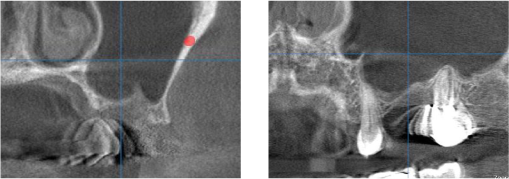

上顎洞までの距離はわずか2mmしかありません。 これではインプラントは出来ません。

下図のように上顎洞に骨になる材用を封入しました。